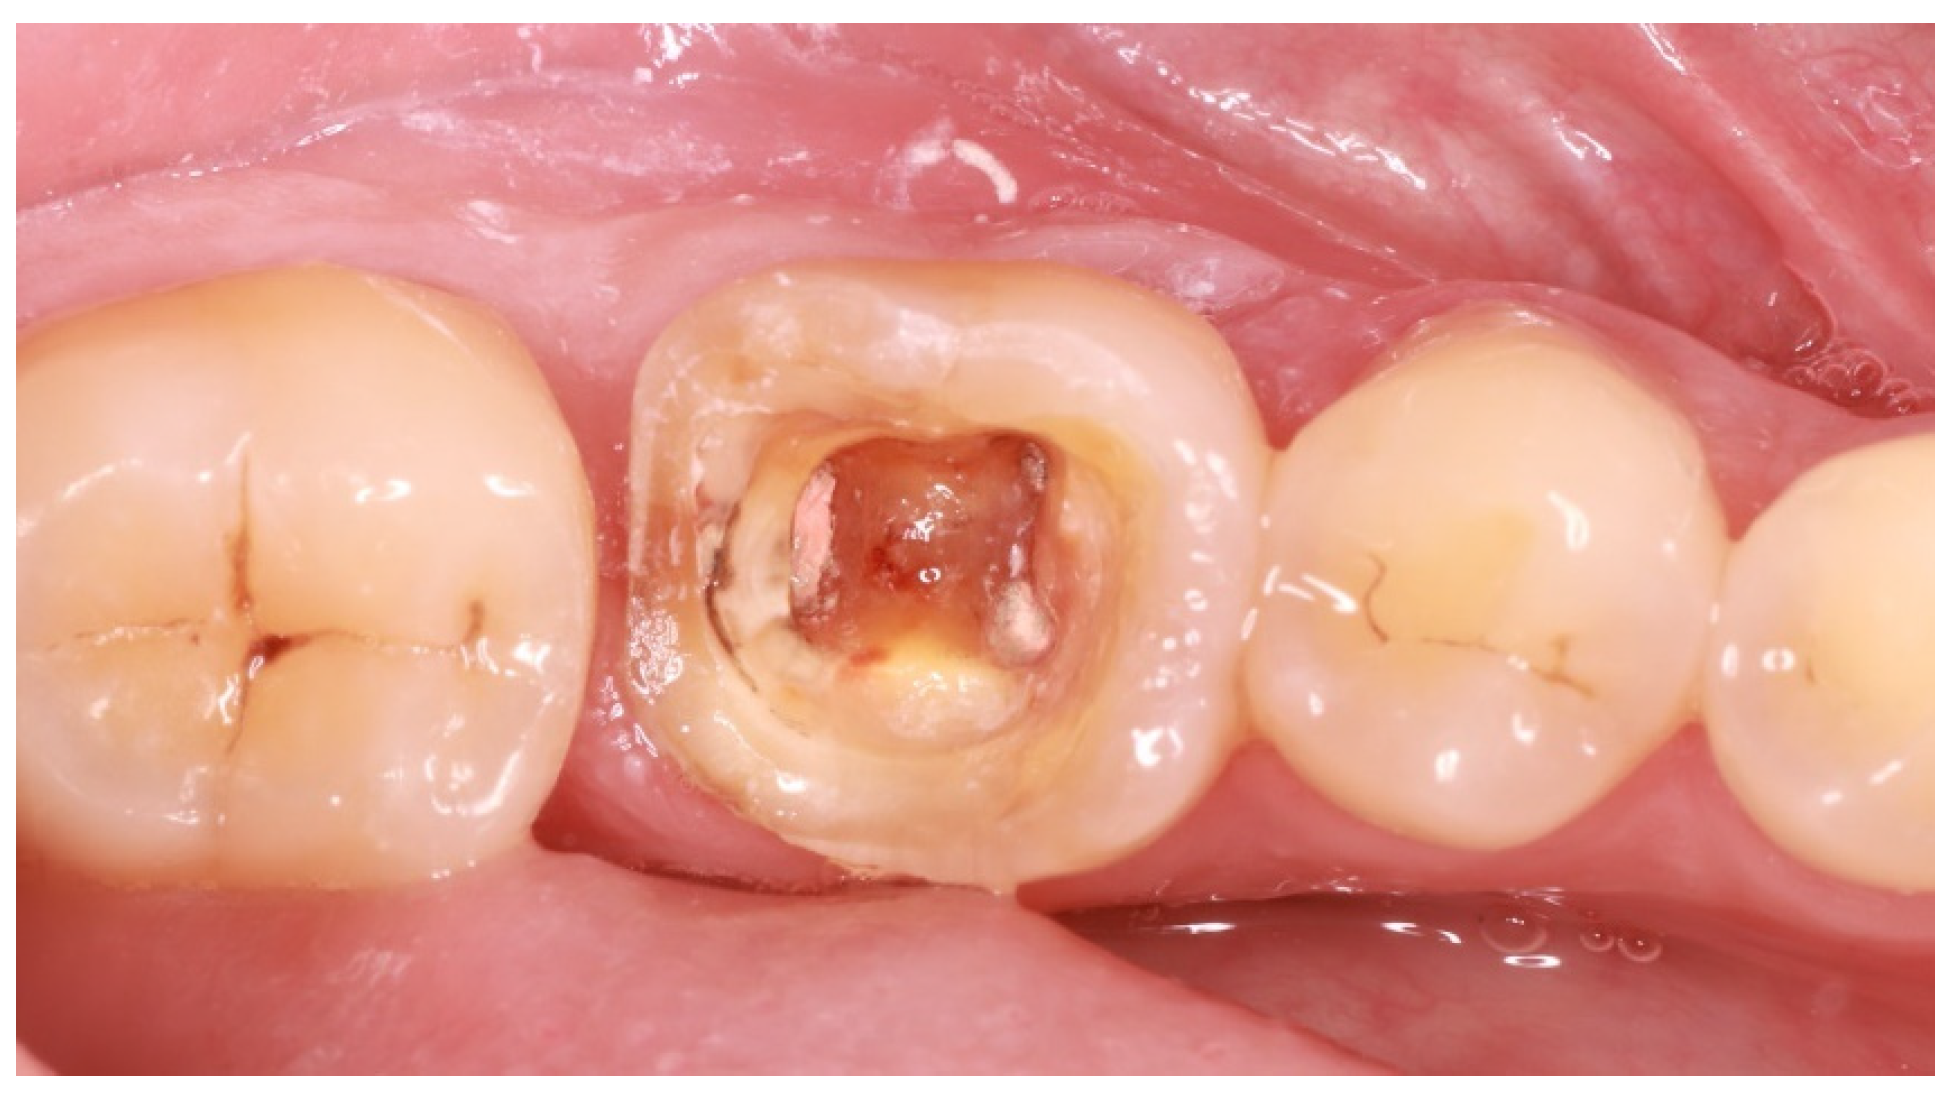

As endocrowns primarily gain retention from adhesive cementation procedures, steps in order to increase micromechanical retention should be incorporated in the applied protocols [11]. In the case described and after the successful endodontic reintervention, the technique of immediate dentin sealing (IDS) was applied on the freshly cut dentin after rubber dam placement [12]. Dentin bonding agent and flowable composite were applied on exposed dentin after removal of the superficial 2 mm of gutta-percha in order to acquire adequate composite resin thickness to avoid microleakage. Cuspal reduction was also performed at this stage so as to both acquire enough interocclusal space for the restorative material of choice, which, in this case, was lithium disilicate, and confirm the presence of dental walls of adequate thickness (Figure 3). Lithium disilicate was chosen because of the positive results regarding the survival rates reported by clinical trials [13].

Figure 3. Confirmation of adequate interocclusal space presence.